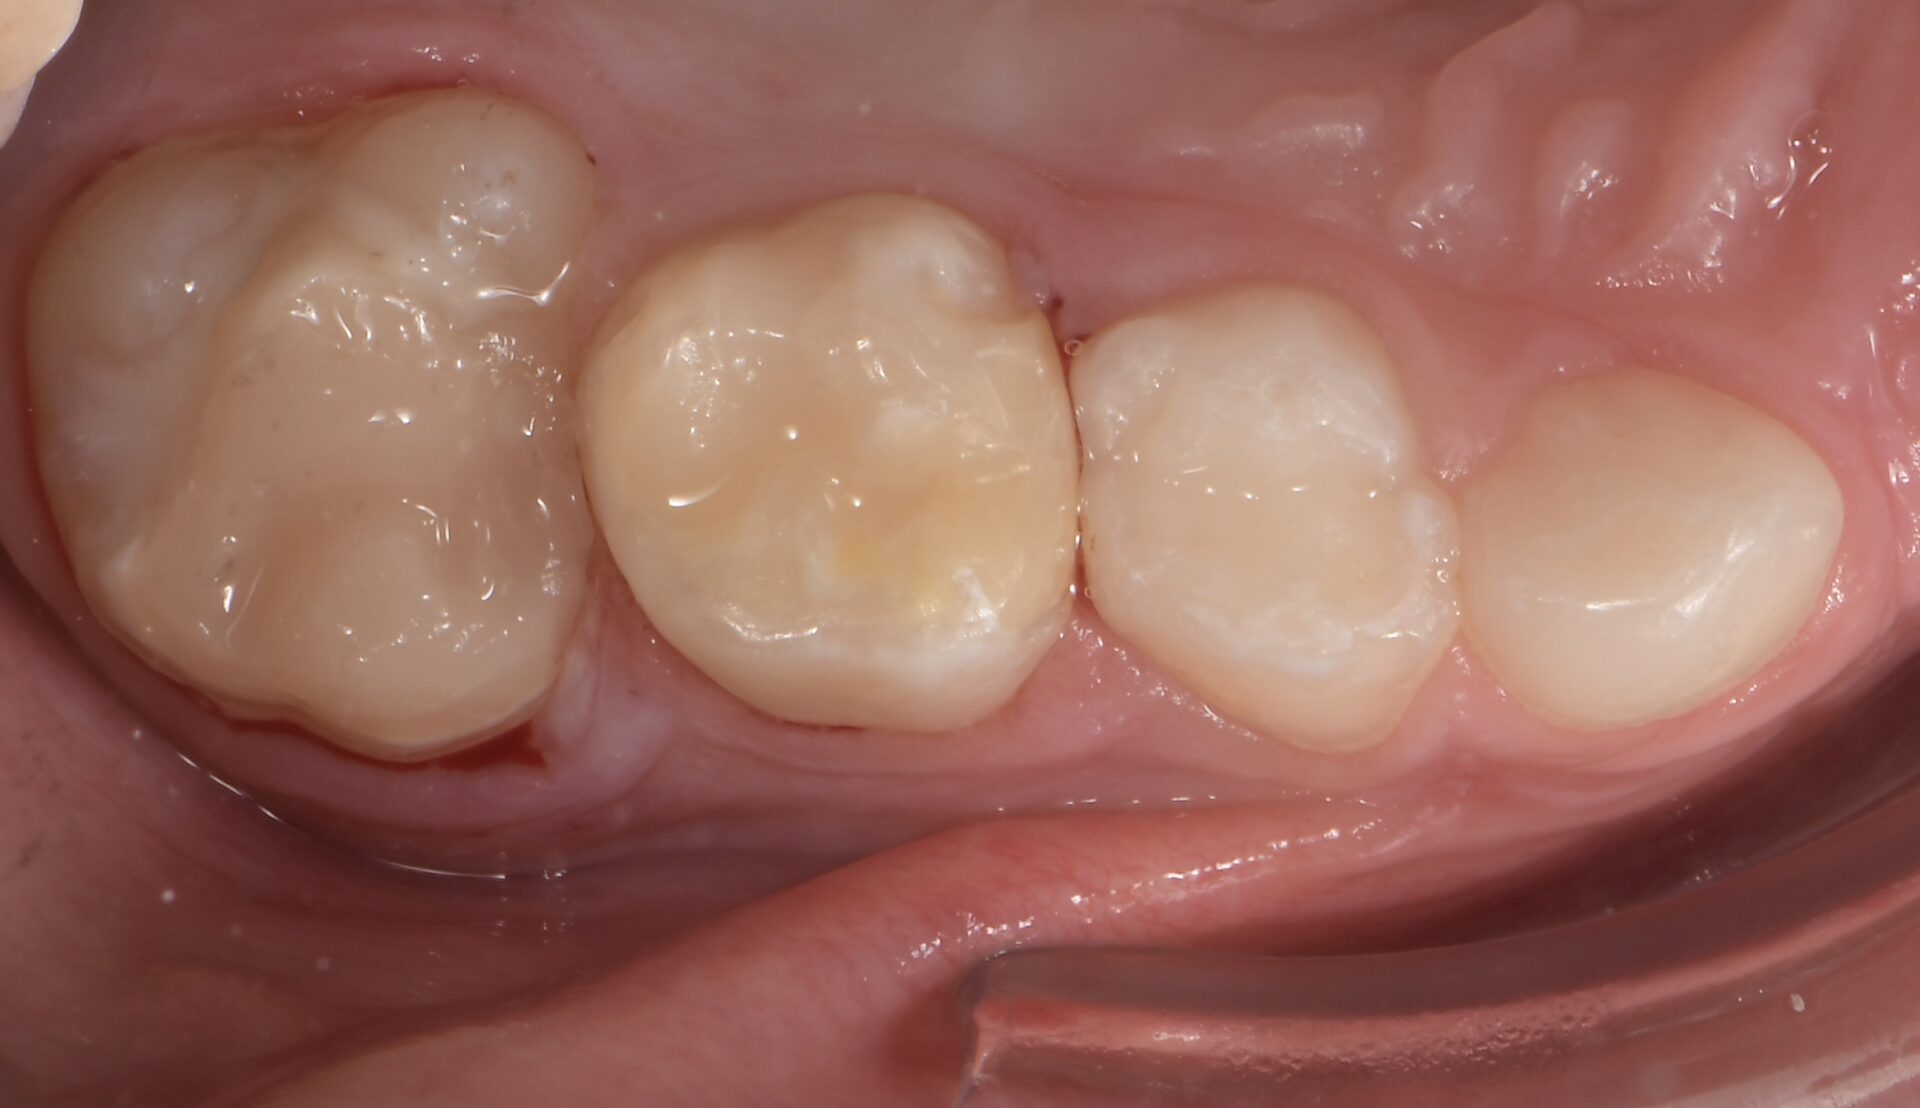

Pour les secteurs postérieurs, en fonction du délabrement tissulaire (PEB ou consécutif à une atteinte carieuse), on optera pour des restaurations directes en composite (Figures 11-12).

formation dentaire pédodontie Figure 11.

formation dentaire pédodontie Figure 12.

Figures 11-12 : Taitement postérieur par résine composite.